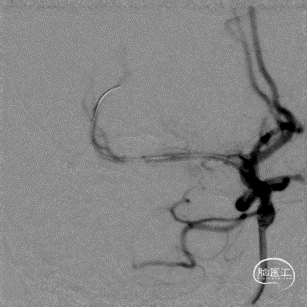

最后工作位造影和正侧位造影,右侧大脑中动脉区域血流恢复,灌注满意。

术后CT无出血,术后患者未诉不适,无新发神经功能症状及体征,继续予以抗栓、强化降脂、调节血糖等治疗。